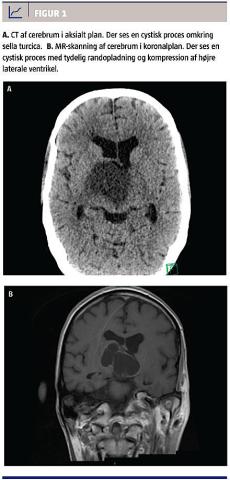

efter genopvarmning, blev der foretaget CT af cerebrum. CT’en viste en 3 × 4 × 6 cm stor central cystisk tumorproces med randopladning (Figur 1). Han fik stigende bevidsthedsniveau og blev med en Glasgow Coma Score på 14 overflyttet til en neurointensiv afdeling. Her blev der fundet endokrinologisk derangering af alle akser og svært nedsat syn. Tumoren blev herefter excideret succesfuldt, men i efterforløbet opstod der et intracerebralt hæmatom og hydrocephalus, EEG’et var abnormt, og der var betydelige iskæmiske forandringer i hjerneparenkymet. I samråd med familien afsluttedes den aktive behandling, og patienten afgik ved døden samme dag.